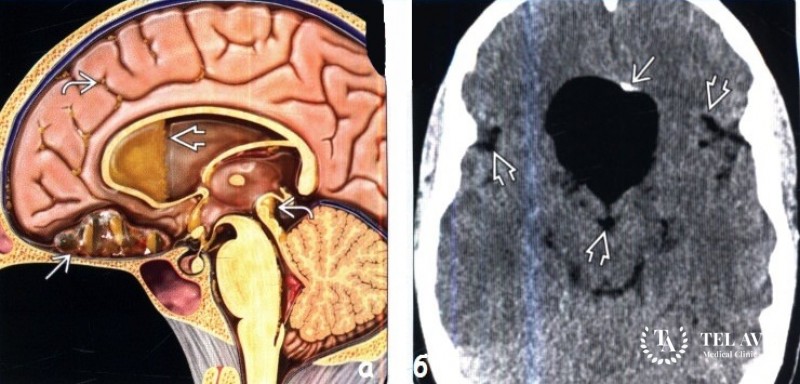

Дермоидные новообразования в мозгу относятся к категории врожденных нарушений. Центральная нервная система ребенка развивается с отклонением от нормы. Определяется наличие кисты в детстве. Образование формируют волосяные фолликулы, хрящи, сальные железы. Нарушенное эмбриональное развитие плода выражается через дермоидную кисту. Иногда серьезная травма становится причиной появления новообразования.